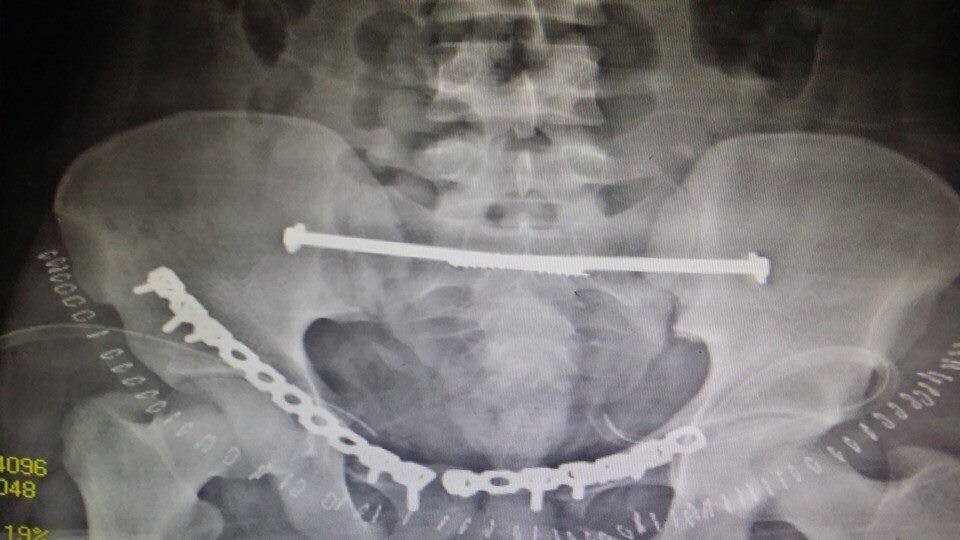

انقاذ مريض تعرض لكسور متعددة بالحوض

المستشفي السعودي الالماني بالرياض يواصل اجراء جراحات الحوض المعقده بنجاح لافت

يواصل المستشفي السعودي الالماني بالرياض اجراء جراحات الحوض المعقدة بنجاح كبير ، جعله من المقاصد الطبية المتميزة ،تعد جراحات الحوض من الجراحات المعقده ، التى تعتبر تحديا كبيرا يواجه جراحي العظام، حيث تتطلب مجهودا كبيرا ومهارة من جراح العظام والفريق الطبى المعاون له . وتعتبر المستشفى السعودى الالمانى بالرياض احد المستشفيات الرائدة ذات السمعة الطيبه فى هذا النوع من الجراحات خاصه وفى جراحه العظام بصوره عامه.

وكان قد حضر مريض الى قسم الطوارىء بالمستشفى اثر تعرضه لحادث سياره ،وكانت حالته العامه صعبه للغايه . وعلى الفور تم عمل الإسعافات اللازمه للمريض وتم دخوله على الفور للعناية المركزه و عمل جميع الفحوصات اللازمه من اشعات عاديه وتلفزيونية ومقطعيه ، حيث تبين وجود كسور متعدده وانفتاح فى الحوض مع وجود نزيف حاد بالحوض قد يؤثر على حياه المريض . وعلى الفور تم إيقاف النزيف بواسطه فريق متكامل من أطباء الاشعه التداخليه.

وبعد استقرار الحاله العامه للمريض ، تمت مناظره الكسور الموجودة من قبل الدكتور محمد فوزي رئيس قسم العظام ، والذى قرر بإجراء تدخل جراحى لفتح وتثبيت الكسور المتعددة بالحوض بواسطه شرائح ومسامير معينه .

وبالفعل تم عمل التحاليل اللازمه ، و دخول المريض لغرفه العمليات ، حيث قام بفتح وتثبيت الكسور . وبحمد الله وتوفيقه تمت العمليات جميعها بالحوض فى جلسه واحده وبنجاح تام ومكث المريض بالمستشفى لعده ايام بعد الجراحة للاطمئنان على الحاله العامه والغيار المستمر على الجروح . وبحمد الله خرج المريض من المستشفى بحاله جيده واستمر فى المتابعة بالعياده الخارجيه بقسم العظام بالمستشفى حتى تمكن من المشى بصوره منتظمة وطبيعية .